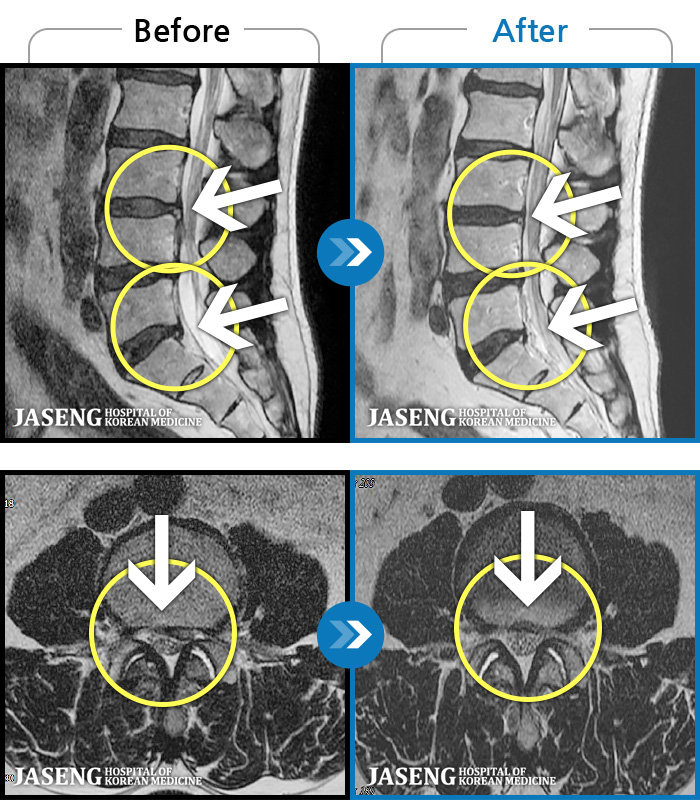

허리디스크

인천 · 강아현 원장

처음 내원시 약 1년 가까이 지속된 허리 통증 및 다리 저림으로 앉아있을 때 통증이 심한 상태였습니다

촬영시기

2020.04.28 ~ 2022.07.30

2022.08.05

조회수 116